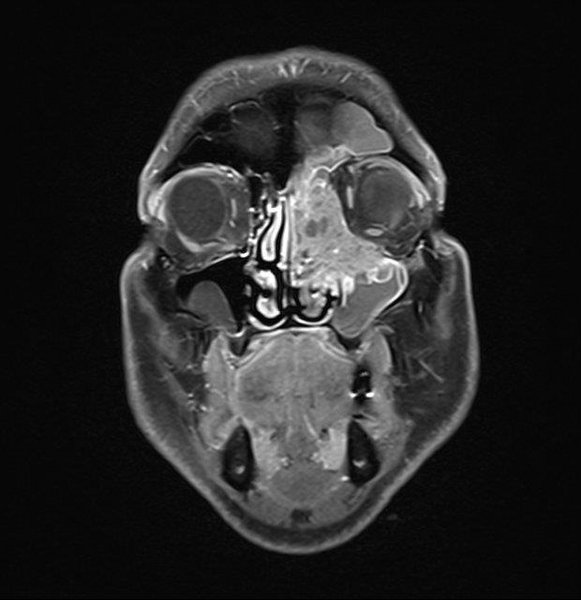

An der seitlichen Schädelbasis sind neben den bösartigen Erkrankungen des äußeren Ohres in besonderem Maße die gutartigen Tumore des Mittelohres, überwiegend sogenannte Paragangliome bzw. Glomustumoren (Bild 2), ein Schwerpunkt unserer Arbeit. Die Diagnostik dieser sehr blutgefäßreichen Tumoren erfolgt mit modernster angiographischer Technik in der Neuroradiologischen Klinik am Katharinenhospital. Dort werden dann auch in Vorbereitung auf die Operation gezielt die zuführenden Blutgefäße verschlossen (Embolisation). Die den Tumor umgebenden wichtigen Hirnnerven (Gesicht- und Zungennerv, die Schlucknerven und der Schulternerv) können durch ein elektrophysiologisches Monitoring während der Operation kontrolliert und ihre wichtigen Funktionen erhalten werden.